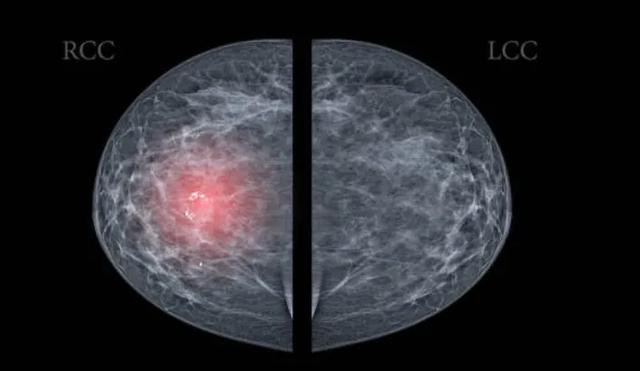

乳腺超声报告,标注“不典型增生”

乳癌发展就像“种子发芽”,最初可表现为乳腺导管或小叶不典型增生。但反过来,并不是所有的乳腺不典型增生都会癌变。

重庆大学附属肿瘤医院肿瘤内科主任王东林提醒,这类增生虽不具有典型的乳腺癌临床特征,但也多表现为乳房肿块、乳头溢液,或肿块和溢液同时存在。

• 遵医嘱定期复查:一般不超过6个月就应复查一次。如果存在乳腺癌家族史,更需警惕。

• 避免不良情绪堆积:乳房是情绪的一面镜子,压抑、郁闷都会伤害乳腺。

• 不乱用雌激素:乳腺是雌激素的靶器官,不滥用避孕药物。

• 减少高脂饮食:高脂饮食易使雌激素水平升高,刺激乳腺细胞过度增生。